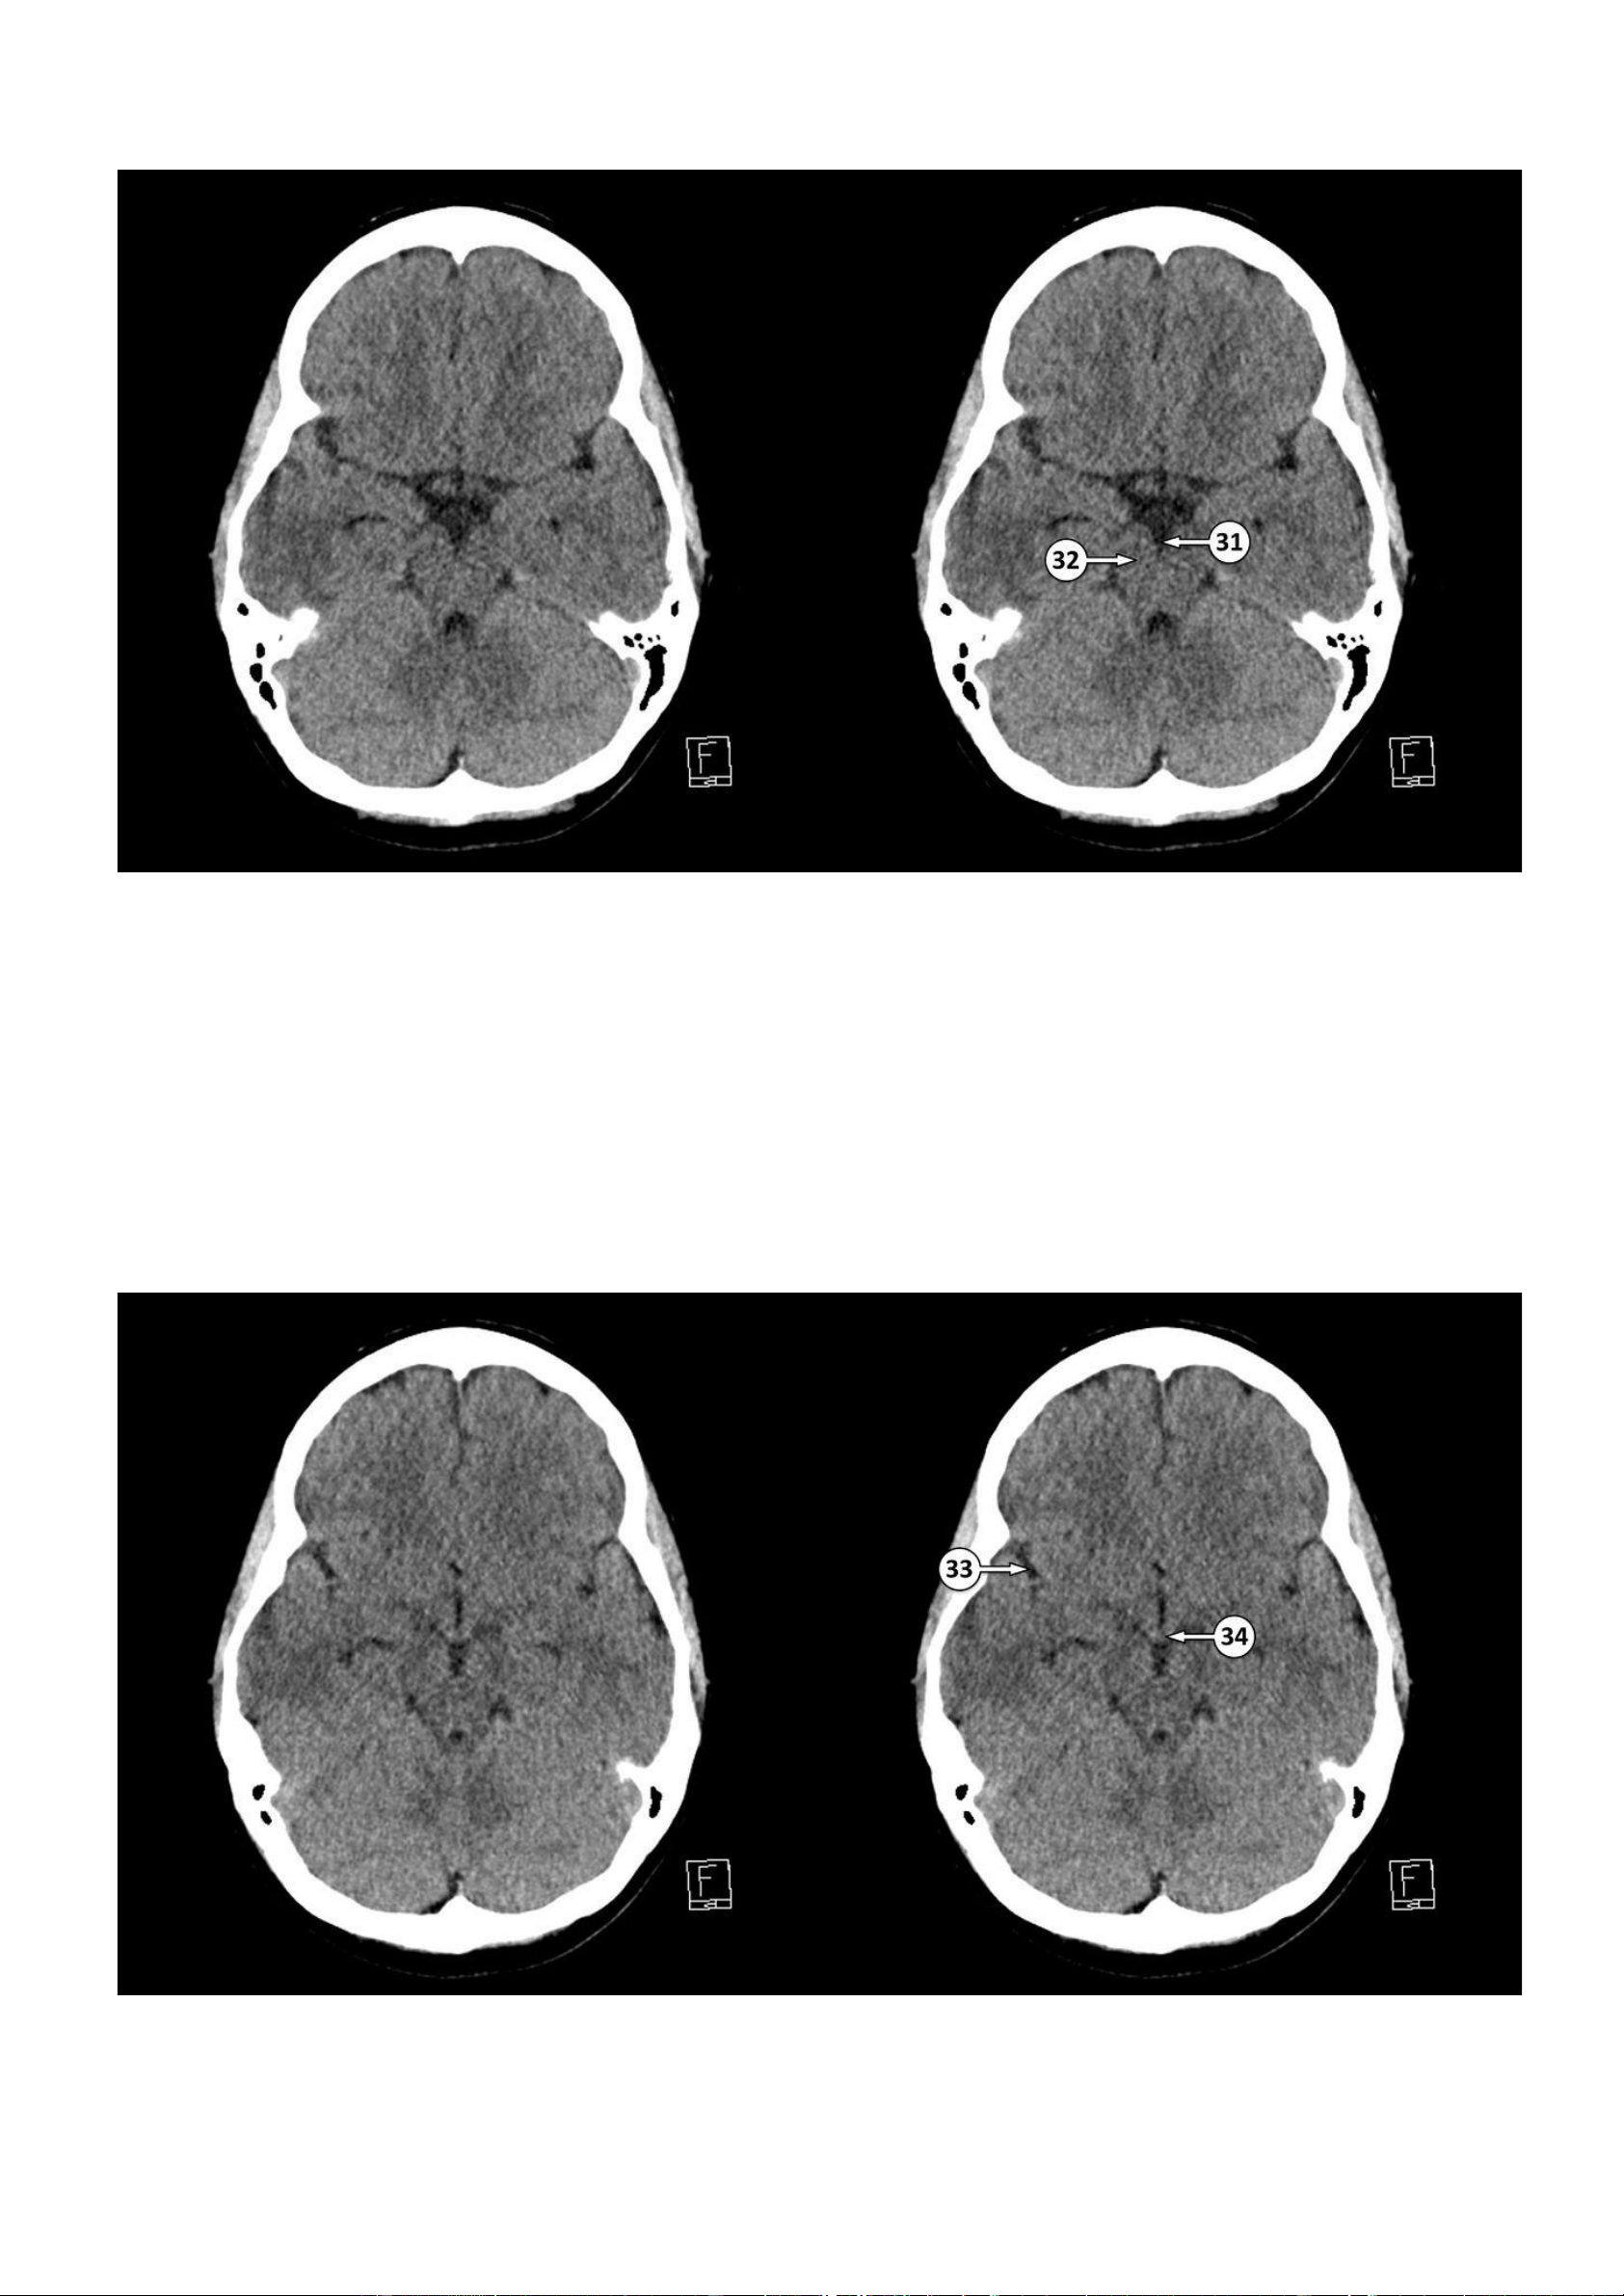

▪ Số 31: Bể gian cuống não ▪ Số 32: Cuống não 33: Rãnh Sylvius 34: Thể vú lOMoAR cPSD| 22014077

▪ Số 35: Khe gian bán cầu ▪ Số 36: Não giữa 37: Bể xung quanh 38: Cống não lOMoAR cPSD| 22014077